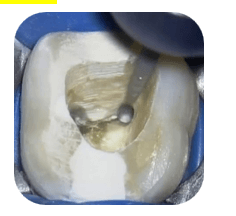

Step 1 — Improve access

Create straight-line access

Step 2 — Create space coronally

Use ultrasonic tips to create a 0.5–1 mm cuff around fragment.